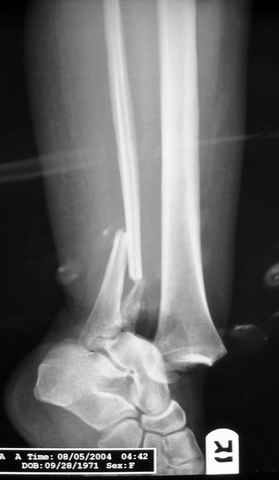

Второй случай сделан из одного разреза

На прямой проекции послеоперационного Рг макроскопически все выглядит очень анатомично, при микроскопическом ( :-)) ) рассмотрении можно все-таки заметить вальгизацию тарана, суставная щель в латеральном отделе сустава несколько уже , чем в медиальном при отсутствии латерального смещения тарана. У меня был аналогичный случай (без LISS , без мини доступа) с вальгусным наклоном тарана при восстановленном ankle mortise при последовательном наблюдении с интервалами в 6-8 недель в послеоперационном периоде отмечалось прогрессирующее сужение суставной щели в латеральном отделе сустава, закончившееся посттравматическим ОА, к счастью боли умеренные, купируемые аналгетиками или своими эндорфинами:-))(активная пациентка, у которой нет времени на болезни....) Какова жизненная ситуация в приведенном вами случае? И последнее, что я хотел бы прояснить для себя - фиксация внутренней лодыжки: я обычно комбинирую фиксацию компрессирующим винтом со спицей - по идее ротационная стабильность должна быть лучше, чем один винт, каковы ваши наблюдения в этом плане?